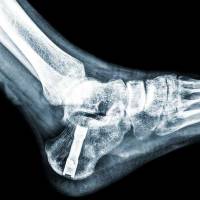

Prothèse de cheville

Prothèses de cheville : alternatives, avantages et risques

L'arthrose de cheville, qu'elle soit d'origine traumatique ou dégénérative, peut fortement impacter la qualité de vie des individus. À l'ICOS Marseille, nous proposons la pose de prothèses de cheville comme solution efficace pour certains cas, bien que la décision nécessite une compréhension appro...

Prothèse de la cheville

Prothèse de la cheville : quand et pourquoi la choisir

Dans le domaine de la chirurgie orthopédique, la prise en charge de l'arthrose de la cheville représente un défi majeur, affectant significativement la qualité de vie des patients. À l'ICOS Marseille, nous nous consacrons à l'étude et au traitement avancé de cette condition, en particulier par le ...